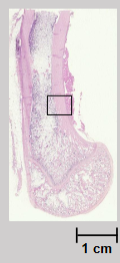

What region of a long bone does this slide show?

The metaphysis.